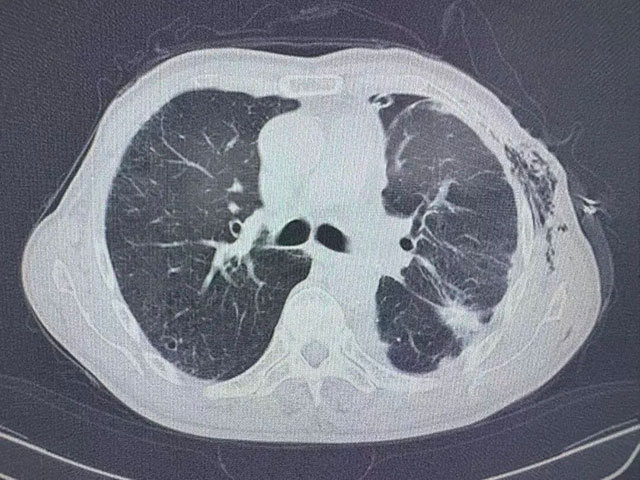

術(shù)后胸部CT

7月9日,劉浩副教授手術(shù)團隊為張爺爺實施胸腔鏡下肺部分切除術(shù)+胸腔積液清除術(shù)+胸膜活檢,成功切除了1.5×1.1×1.0cm大小的浸潤性腺癌病灶,并清除了胸腔內(nèi)積液。術(shù)后病理提示,腫瘤已侵犯肺膜,屬于晚期肺癌,治療預(yù)后不佳。

HITOC第二步:術(shù)后規(guī)范熱藥物灌注

“確定最佳藥物劑量、灌注頻率以及……”術(shù)后恢復(fù)一段時間后,7 月31日,張爺爺接受了關(guān)鍵的胸腔熱灌注化療(HITOC)。復(fù)查顯示,各項指標(biāo)平穩(wěn),僅紅細胞略有下降,對癥處理后迅速恢復(fù)。